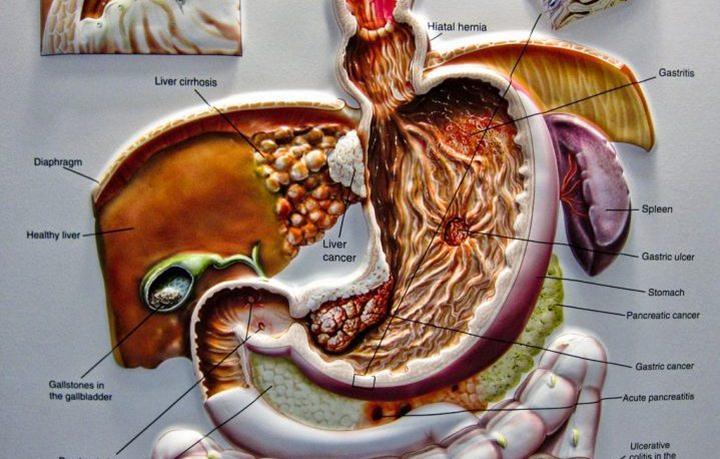

Hepatitis C is the top cause of liver cancer and transplants. A person can catch the virus by coming into contact with blood that has been contaminated. Most of the time, it is spread by unclean needles (drug paraphernalia) or through exposure to previously used tattoo needles. However, it...

Dealing with cancer is difficult, but when the verdict is pancreatic cancer, the survival rate is only 25 percent for the first five years after the diagnosis. Like all other cancers, staging occurs from the beginning. The oncologist will base the stages upon various factors, such as if the...